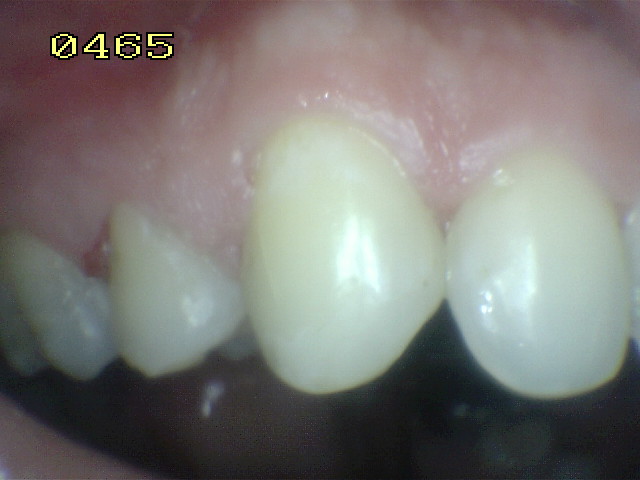

Técnica de aplicación profesional del barniz fluorado (Clinpro White Varnish)

4. Aplique una capa delgada de barniz de una sola vez, lo más rápido posible (figura 2) notará que el barniz se vuelve más firme, porque seca muy rápido en ambientes cálidos ó en contacto con los dientes.

5. Secuencia de aplicación:

• Arcada superior desde las molares hasta los incisivos: caras vestibular, proximal, oclusal  y palatino

• Arcada inferior desde las molares hasta los incisivos: caras vestibular, proximal, oclusal  y palatino (figura 3)

Figura 3

Figura 2